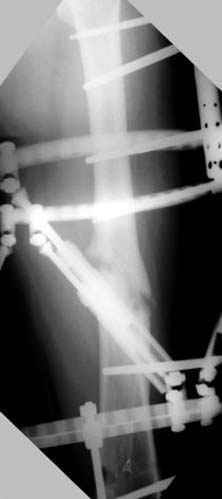

Отправитель: Djoldas Kuldjanov 23 Ноябрь 2004, 18:21

пластическая модель; и коррекция бедра аппаратом Илизарова.

Имею другие снимки тоже, получится как отчет о моей работе.